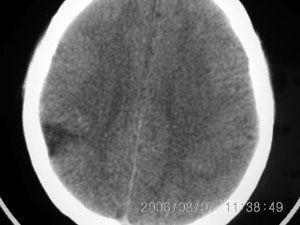

标题: CT4285:头部病变,女 21岁

女 21岁 发作性面色发白一年,每次发作仅数秒钟

左颞顶叶不规则低迷度影边界尚清楚,岁数年轻,应考虑脑血管畸形。建议强化或核磁,进一步检查。

局限性脑软化灶,右侧侧脑室后角受吸引,略有拉伸。考虑动静脉畸形。